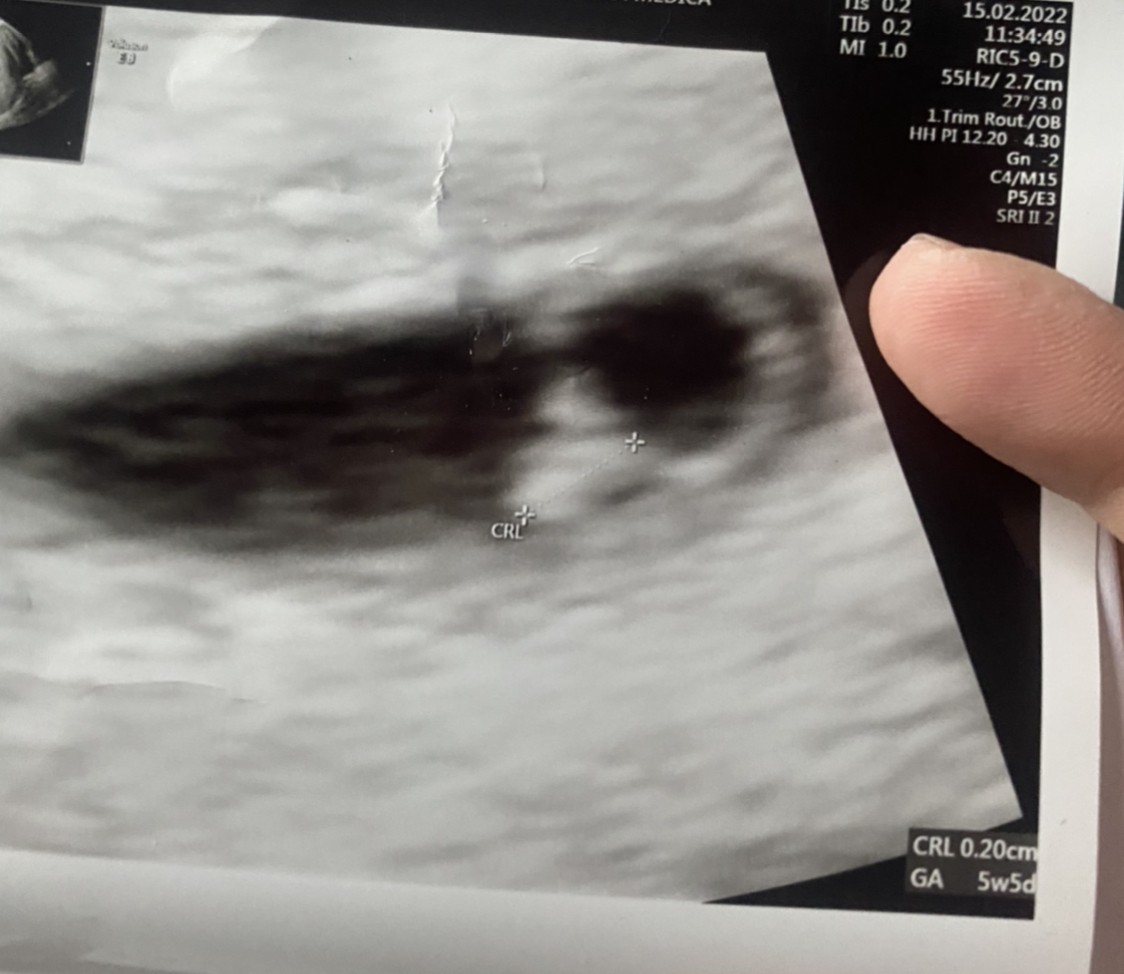

Mały wielki człowiekNaprawdę na tych zdjęciach niewiele widać (na ekranie ledwo obraz był lepszy). Lekarz powiedział, ze to jego zdaniem pierwszy dzień, w którym można było zarodek z serduszkiem złapać.

a który tydzień ?Naprawdę na tych zdjęciach niewiele widać (na ekranie ledwo obraz był lepszy). Lekarz powiedział, ze to jego zdaniem pierwszy dzień, w którym można było zarodek z serduszkiem złapać.